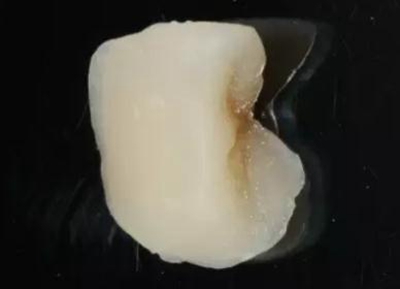

最后附昨天備牙,今日戴牙的一個美塑嵌體。